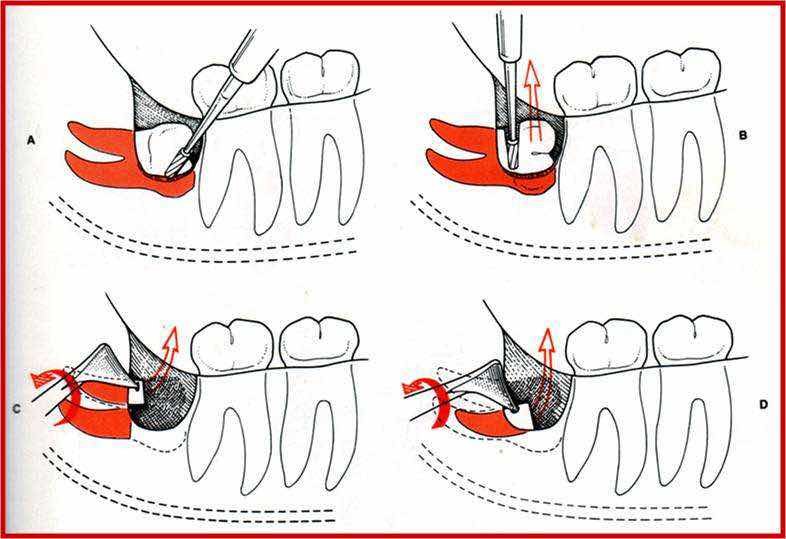

关于干槽症致病机制的各种学说,主要集中在创伤以及感染因素致病方面。由于缺乏足够的证据,关于确切的致病原因未能达成一致意见,唯一明确的是所有这些致病学说均不能全面满意解释干槽症的发病及临床现象,导致临床无法形成具有针对性的预防措施。有认为损伤严重或创口开放过大可能导致干槽症,但无法解释颌骨囊肿手术骨创伤大、牙龈瘤切除后大面积骨面暴露却从未发生干槽症。以往,所谓损伤严重的概念主要是指骨切除范围过大,如低位骨埋伏阻生需要大量切骨,故损伤大,对于如何造成骨损伤的方式关注不够。有观察到经验欠缺的低年资医生,实施手术后有较多干槽症出现。但即使高年资医生手术也难免干槽症的发生,骨损伤与干槽症关联性的脉络并不清晰。创伤将造成骨细胞受损,引发炎症反应并释放细胞介质,导致纤维溶解活动,增加干槽症发生的风险。所有涉及骨的手术创伤均有可能出现上述现象,然而干槽症仅见于拔牙手术后,尤其是下颌智齿拔牙手术后多见,干槽症似乎是拔牙后的专属并发症。疑问随之而起,即损伤严重性的确切含义是什么?除了切骨量大、骨创面大等显而易见的表象,是否有代表骨损伤严重性的实质被表象掩盖而忽略?而可能正是这种实质能够提供干槽症发病的确切答案。干槽症的病理实质是局限于牙槽窝骨壁的骨坏死,但是骨坏死的机制并未明确。骨髓炎的骨坏死发生于骨髓炎起病后的2 ~ 3 周,呈团块状,范围较广。干槽症骨坏死发生于术后的1~ 2 d,几乎随着手术之后立即出现,并局限于牙槽窝骨壁。两种骨坏死的形式及形成时间存在明显区别,用骨髓炎感染性疾患的机制并不能满意解释干槽症的骨坏死现象。纵观常规的阻生齿拔牙方法,均难免骨损伤,从表象上看造成骨损伤的形式明显不同。锤击拔牙以锤敲击骨凿或牙挺实施切骨、劈冠、楔入牙周增隙,锤击力经由骨凿、牙挺传导到牙体,再进一步传导至牙槽窝骨壁,或直接经由牙挺达到骨壁,造成对于骨面的暴力冲击,骨质可能发生压缩或挤压、变形等类似挫伤的改变。由于牙釉质的硬度高于骨质,牙骨质硬度与骨质相当,当试图锤击牙挺楔入牙周时,势必发生牙槽窝骨壁骨质和牙骨质的压缩变形扩大空间,牙挺才能进入牙周产生增隙效果。当这种骨质压缩变形超过一定限度,可能使骨质表面坏死,形成骨挫伤,即所谓干槽症。拔牙时的外力锤击造成骨质损伤坏死的骨挫伤,紧随外力的施加立即发生,可以比较合理地解释干槽症骨质坏死的发生、形式以及发病的迅速性。骨挫伤是近二十多年才提出的骨质损伤概念,骨挫伤的前提条件,是有外力的钝性打击。骨挫伤的主要症状是疼痛、关节不稳等。干槽症与骨挫伤在疾病的发生及某些临床表现方面有一定相似性。干槽症也是起于组织遭受钝性打击之后,以疼痛表现为主要症状。当锤击力经牙传导到骨壁的过程中,牙碎裂、移动时可能吸收部分能量,力量存在衰减;或楔入牙挺增隙时锤击力是侧向剪切力,力的效应止于牙槽窝骨壁,使干槽症骨质坏死局限在骨壁表面,而且皮质骨骨壁没有中断,所以常规影像学平片或CT检查不能显示出骨质的病理性改变。涡轮机拔牙,通过车针的高速旋转切割骨质和牙体,虽有水冷,也仍然存在骨质损伤。与锤击拔牙的不同之处,在于涡轮手机拔牙,骨损伤的形式是车针的切割伤,与外力击打造成的骨质挫伤存在显著区别,缺乏骨质压缩变形坏死的基础,也就杜绝了干槽症的发生。

颌骨的骨质密度以及血供呈现不均匀分布,下颌磨牙区特别是下颌第三磨牙区的骨质密度较高、较少血管分布,在骨质遭受外力击打发生压缩变形时,可能容易出现因骨质挤压而破坏局部血液循环进而导致骨质坏死。加之下颌第三磨牙拔除困难复杂,需要较多的锤击,增加了骨质发生压缩变形

坏死的概率。合适的解剖特点以及锤击力的施加,是干槽症发生两个先决条件。在解剖特点的基础上,外力的钝性击打作用更容易发生骨挤压,变形坏死的骨挫伤表现。其他部位的复杂牙齿拔除,如果具备以上解剖特点及受力形式,也可能发生干槽症。